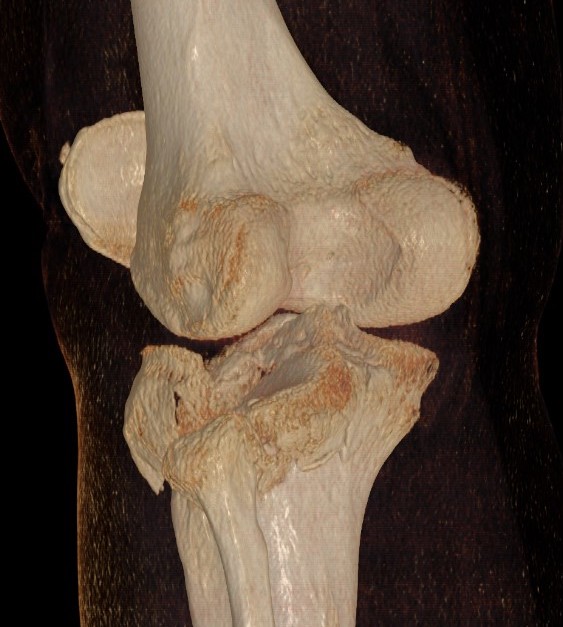

3 column concept of tibial plateau fractures

Luo et al. Orthop Trauma 2010

- introduces the 3 column concept

- medial column / lateral column / posterior column

- posterior column can be splint into medial and lateral fragments (posterolateral / posteromedial)

- imporant as any surgery must address these fragments

- typically require additional posteromedial or posterolateral approaches